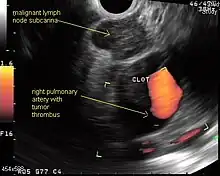

Endobronchial ultrasound (EBUS)

As mentioned in the table, EUS cannot reliably access right sided paratracheal lymph node stations 2R and 4R and may not be optimal for the left sided paratracheal lymph node stations either. An adaptation of the endoscopic ultrasound scope originally designed for the gastrointestinal tract is known as endobronchial ultrasound (EBUS). The instrument is inserted into the trachea rather than the esophagus. There are two types of EBUS bronchoscopes available: radial catheter probe and convex probe EBUS (CP-EBUS),[33] but only the latter concerns us here. Early experience with mediastinal staging by CP-EBUS appears very promising with sensitivities ranging from 92 to 96 percent in 4 series comprising 70 to 502 patients.[34][35][36][37]

Combined ultrasound

Many patients will, if given a choice, prefer an instrument which is inserted into the esophagus (EUS) over one which is inserted into the trachea (EBUS). Furthermore, many patients with suspected lung cancer will have other smoking related illnesses, such as emphysema or COPD, which makes a bronchoscopy-like procedure (EBUS) a higher risk than an upper endoscopy through the esophagus (EUS). An area of active and emerging research concerns the value of combining EUS and EBUS in a single session, one specialist following the other, or -even more convenient- a dual trained operator doing one or the other – or both- as needed.

EUS-FNA and EBUS-FNA are complementary techniques. EUS has the highest yield in the posterior inferior mediastinum, and EBUS is strongest for the superior anterior mediastinum. Some lymph node stations can only be accessed by one method and not the other (for example, station 2 and 4 L and 3 are hard or impossible to see by EUS, stations 5 and 8 cannot be biopsied by EBUS). Together, EBUS and EUS cover the entire mediastinum (except possibly station 6) and complete mediastinal staging should be possible with a combination of these two procedures. This combination could conceptually eliminate the need for most surgical mediastinoscopies and in fact be more comprehensive.

When combined, this approach has been termed "complete medical mediastinoscopy." EUS-FNA with EBUS may allow near-complete, minimally invasive mediastinal staging in patients with suspected lung cancer [38]